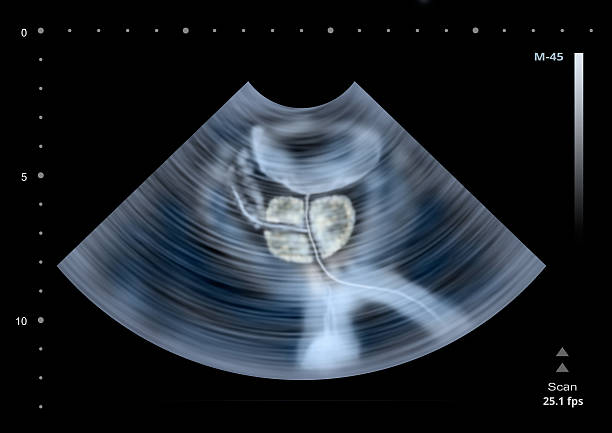

남성 생식기의 요로계와 직접적 연관이 있는 전립선은 사과 모양으로 배꼽 아래쪽에 위치해 있으며 상당히 중요한 역할을 하고 있습니다. 전립선은 사정을 조절하고, 정자의 움직임을 돕는 전립선 분비액을 만들어냅니다. 이 분비액은 정자의 영양 공급과 이동에 필수적인 성분을 포함하고 있습니다. 또한, 전립선은 방광을 둘러싸고 있는 방광 경화근과 골반 바닥 근육에 대한 지지 구조 역할을 할 수 있어 상당히 중요하나 전립선에도 암이 발병될 수 있어 초기에 원활한 대응을 해야만 합니다. 그럼 이번 시간에는 전립선암 초기증상에 대해 자세히 정리해보겠습니다.

전립선암 초기증상